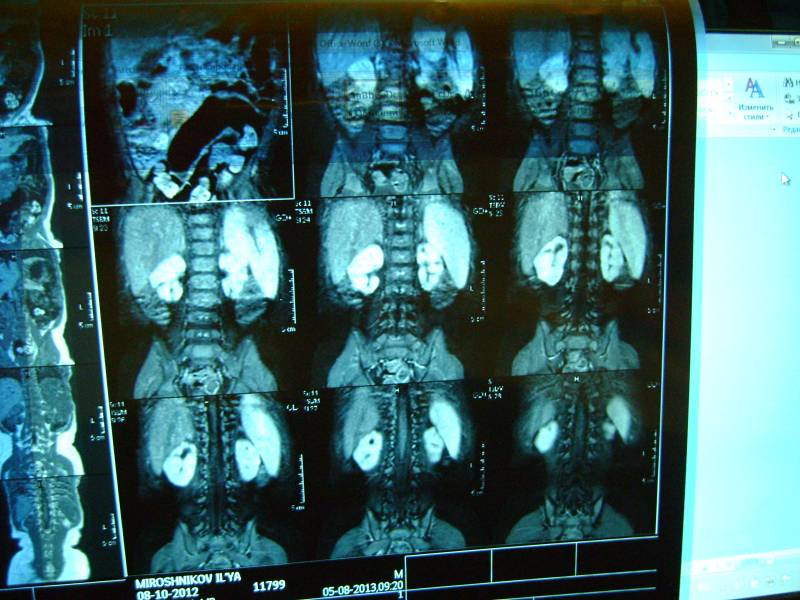

Уважаемый доктор просим посмотреть снимки и нашего сына! Возраст 10 мес. два близнеца однояйцевых у одного поликистоз у второго нет. Можно ли понять тип поликистоза детский или взрослый? Можно ли отправить диск со снимками мрт Вам если можно то куда? К генетикам пойдем в ближайшую среду. Заранее огромное спасибо!!! Попробуем еще фото выложить

Добавляем еще фото